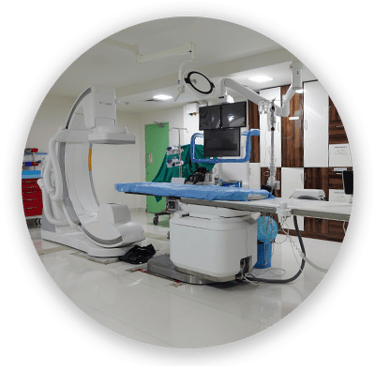

JJ Hospital is a forward-thinking healthcare center committed to providing accessible, affordable, and high-quality medical services to individuals and communities. Our team of experienced and compassionate doctors works together to deliver advanced treatments, patient-focused care, and innovative medical solutions. Equipped with modern technology and a holistic approach to healthcare, we offer a wide range of medical services while maintaining excellence in every procedure. From preventive care and diagnostics to specialized treatments, we aim to provide reliable and affordable healthcare for everyone.Write your text here...

Master on Surgeries

Complex trauma

Complex trauma refers to severe injuries involving multiple fractures, joints, or soft tissues, usually due to accidents or high-impact trauma. It often requires surgical fixation using plates, screws, or rods to stabilize bones.

Arthroscopic surgery

Arthroscopy is a minimally invasive procedure where a small camera (arthroscope) and instruments are inserted through tiny incisions to examine or repair a joint

Total Knee Replacement (TKR) and Total Hip Replacement (THR)

Joint Replacements